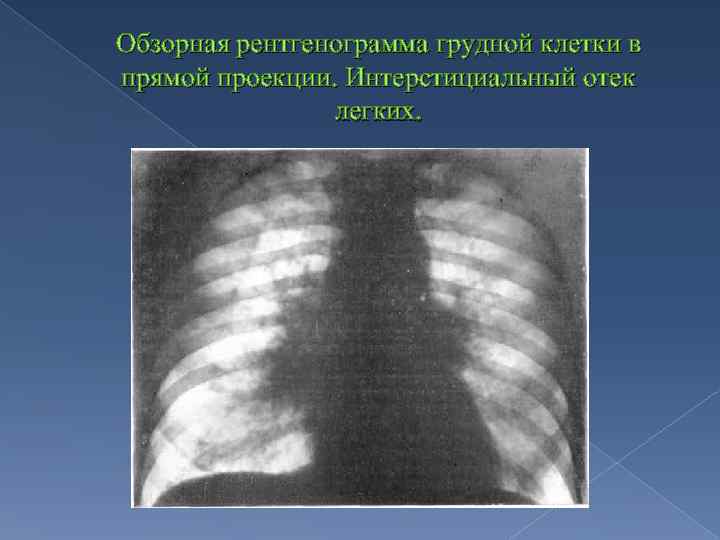

Что такое малоконтрастная рентгенограмма органов грудной клетки